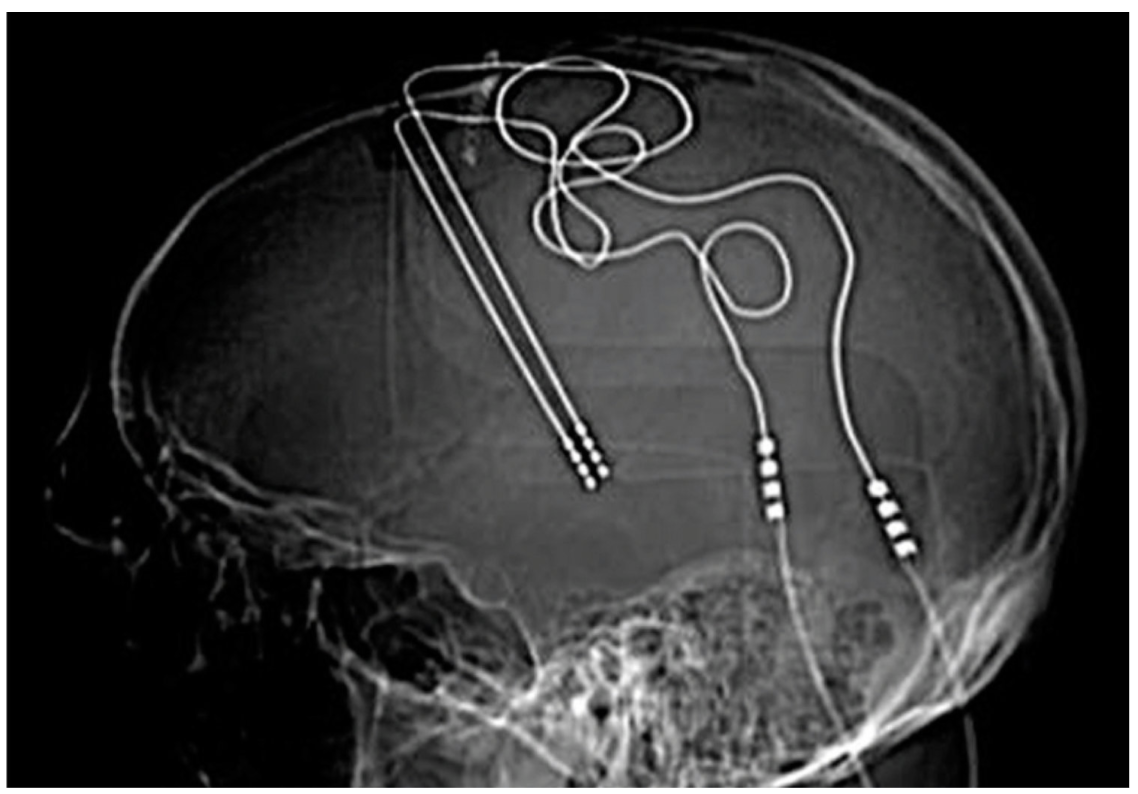

Deep Brain Stimulation (DBS) uses application of electrical current to change neuron function via electrodes directly implanted into the brain. DBS is commonly used for movement disorders like Parkinson’s disease and in some cases of severe, treatment refractory depression. Electrodes for DBS treatment require a neurosurgical procedure with the patient awake, under local anesthesia, so they can give feedback to the surgeon as they test each electrode. Two implants, with a total of 5-20 electrodes, are placed at target sites in each hemisphere of the brain. During the procedure, the patient tells the surgeon if movement is easier, if they feel different, etc. and the surgeon can select which 2-4 electrodes should be used to produce the most beneficial effect. The surgeon then places connecting wires from the implants inside the brain out through the skull and under the skin to a pacemaker-like device on the chest wall; this device interfaces with a handheld device in the physician’s office, where they can change the intensity and duration of electrical stimulation.

This X-ray image represents advanced neurotechnology like Neuralink, used for brain-machine interfaces, psychiatric treatments, and cognitive enhancement.

Image Source: Chen, 2019.